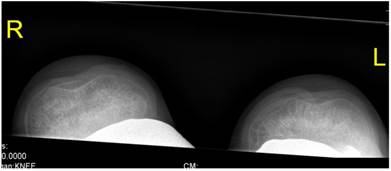

Sky line-view in a male patient aged 19- years showed bilateral and symmetrical trochlear hypoplasia (flattened trochlea) with subsequent development of patellar instability (fig 9). Sky-line view in a-7-year-old boy showed severe trochlear dysplasia with subsequent patellar mal-tacking associated with significant osteoporosis (fig 10).

Fig 9

Sky line-view in patient showed bilateral and symmetrical trochlear hypoplasia (flattened trochlea) with subsequent development of patellar instability in a 19-year-old patient.

Fig 10

Sky-line view in a-7-year-old boy showed severe patellar- trochlear dysplasia with subsequent patellar mal-tacking associated with significant osteoporosis.